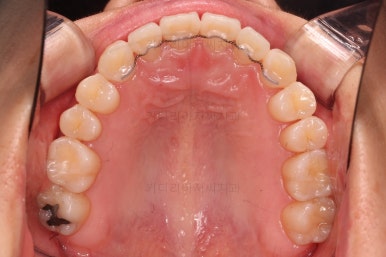

두번째 세트를 진행 중입니다.

부족한 부분을 좀 더 맞춰주고요.

마무리를 하게 됩니다.

철사교정과 마찬가지로 앞니쪽에 유지장치를 구성하고 치료를 종료합니다.

매우 가지런해졌고요.

맞물림도 좋아졌고, 중앙선도 잘 맞춰졌습니다.